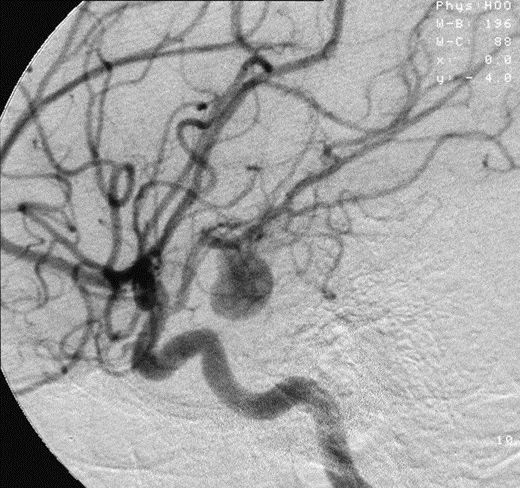

近日,辽宁大连的一位55岁张女士在家庭聚会时,兴致高昂地唱了一首《青藏高原》,并且挑战飚高音,结果突然出现剧烈头疼、恶心呕吐等症状。

送医后通过全脑血管造影检查发现,张女士动脉瘤破裂,而后经过2小时的介入手术,破裂的动脉瘤被妥善处置,转危为安。